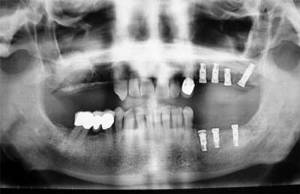

És una especialitat transversal de l’Odontologia en què participen de forma preferent la cirurgia bucal i la prostodòncia, i la seva finalitat és restaurar la pèrdua d’una dent, de diverses dents o de totes les dents mitjançant una pròtesi que es recolzi en implants osteointegrats col·locats als maxil·lars.

La incorporació de la implantologia a la pràctica odontològica ha representat un gran avanç per a la rehabilitació-restauració de la pèrdua de les dents. Abans s’instal·laven pròtesis recolzades en altres dents o sobre la mucosa bucal, produint-se tota mena de complicacions. Els implants dentaris són fixacions (tornillos) de titani amb superfícies bioactives que es col·loquen als maxil·lars (intraòssies), imitant una arrel dentària encara que el seu comportament és diferent.

Normalment es prefereix col·locar pròtesis fixes sobre els implants (atornillades o cementades), encara que també poden indicar-se pròtesis removibles (de posar i treure) però que estan recolzades sobre els implants i no sobre altres dents o sobre la mucosa bucal i l’os alveolar.